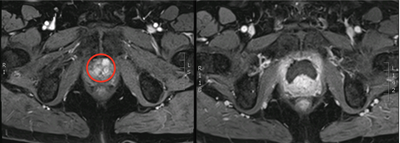

Figure 1: Left - red circle highlighting anterior tumour; right

- post cryotherapy dynamic contrast enhanced MRI showing ablated area.

The anteriorly located tumours are ideal for cryotherapy. It is also possible to treat tumours within the posterior zone, however, there is a potential for more side-effects as the ice ball needs to cover the entire lesion and may transgress into the rectum, leading to an increased risk of developing a rectal fistula. These may be better treated by an alternative energy source such as high intensity focused ultrasound (HIFU).